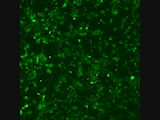

The green dots are stem cell-derived nerve cells with a calcium dye. The activity of the network shows that after two weeks in culture, the nerve cells are “thinking”, even partially synchronously.